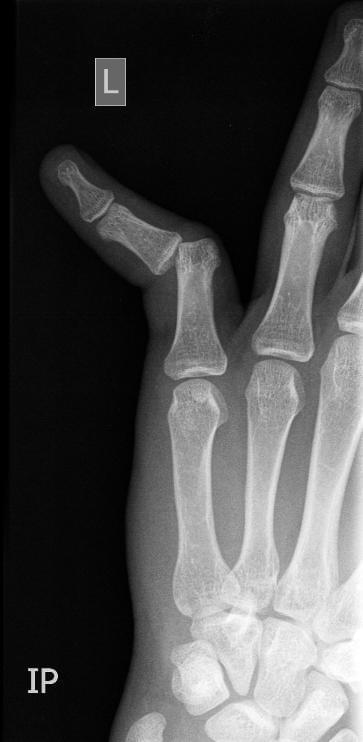

Palec

Co zrobiłeś? Co lekarze Ci z tym zrobili i jaka diagnoza?

Wybicie. Nastawili mi to w szpitalu i wysłali do domu. Zdjęcia są moje, to nie fake.

Róg mi się przekręcił i zablokował przedni hamulec. I zaliczyłem piękny lot.